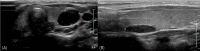

Primary hyperparathyroidism (PHPT) is a hypercalcemia disorder with inappropriately normal or increased serum parathyroid hormone (PTH) levels resulting from excessive secretion of PTH from one or more of the parathyroid glands. PHPT is uncommon in infants and children, with an estimated incidence of 2-5 cases per 100,000 persons. Patients with PHPT usually present with bone pain, urolithiasis, or nephrolithiasis, as well as nonspecific symptoms such as fatigue and weakness. Asymptomatic hypercalcemia may also be detected incidentally. Only a few cases of pediatric PHPT have been reported in Korea. We present three patients (a 9-year-old girl, a 14-year-old boy, and a 14-year-old girl) with PHPT who manifested variable clinical features of hypercalcemia. The first and second patients each had a parathyroid adenoma and presented with abdominal pain caused by pancreatitis and a ureter stone, respectively. The third patient had an ectopic mediastinal parathyroid adenoma and presented with gait disturbance and weakness of the lower extremities. All of the patients underwent surgical resection of parathyroid adenoma, and their serum calcium levels subsequently normalized without medication.